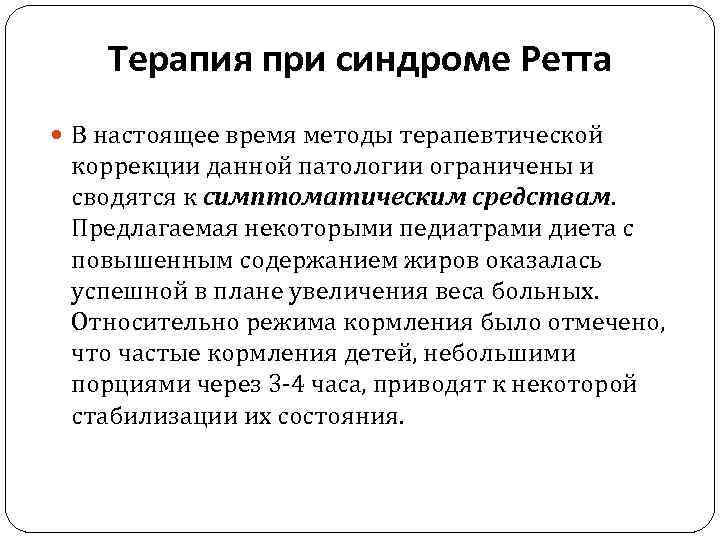

Терапия при синдроме Ретта В настоящее время методы терапевтической коррекции данной патологии ограничены и сводятся к симптоматическим средствам. Предлагаемая некоторыми педиатрами диета с повышенным содержанием жиров оказалась успешной в плане увеличения веса больных. Относительно режима кормления было отмечено, что частые кормления детей, небольшими порциями через 3 -4 часа, приводят к некоторой стабилизации их состояния.